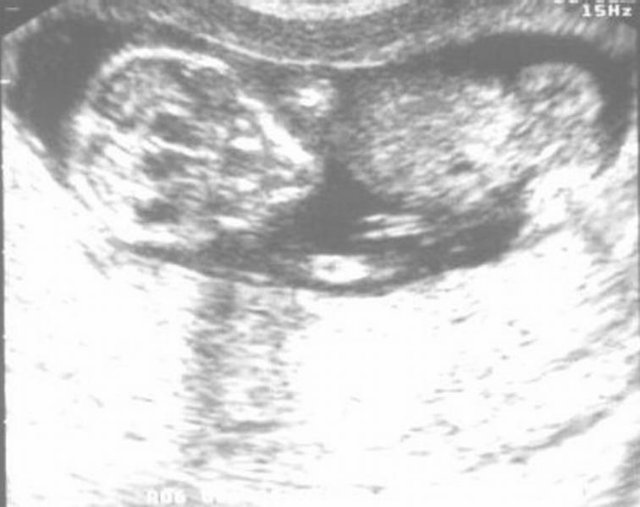

Hier sieht der kleine aus wie ein ALIEN!!!! Ultraschall-Bild vom 07.01.2004